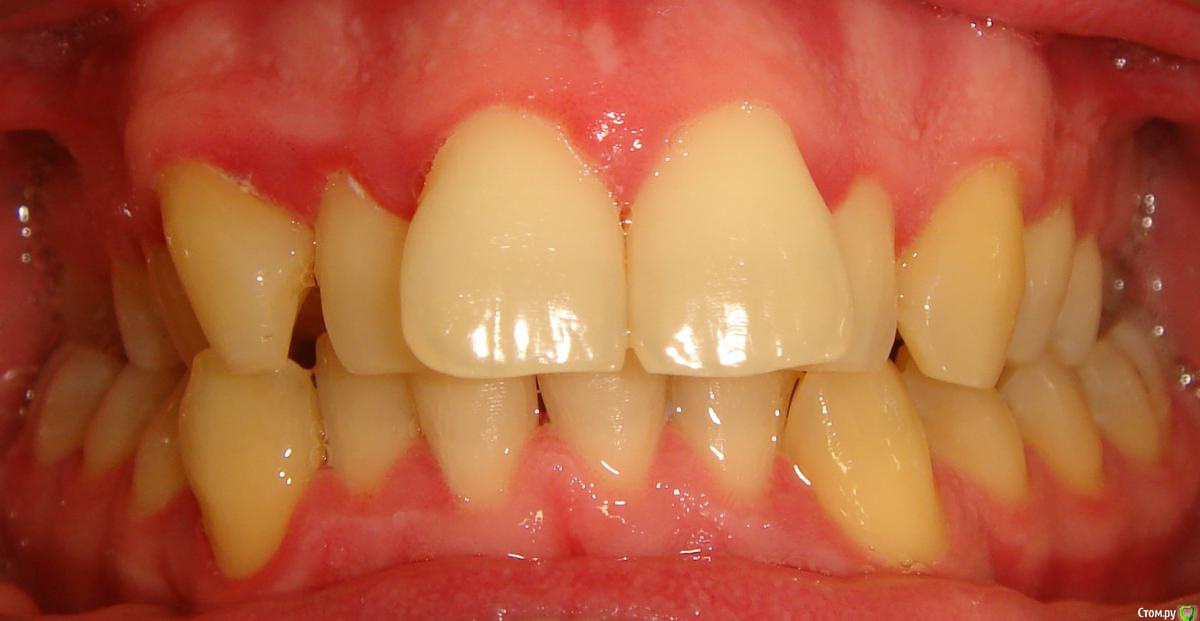

Здравствуйте, Коллеги. Вот такой вот случай, пациент 32 года. Изначально, хотел дистализировать в первом сегменте с целью апрайтинга 13 - 16, провести апрайтинг боковых зубов н/ч, затем САРПЕ и MEAW, понятно, что восьмерки долой еще до лечения. Но потом увидел форму корней 37, 47 (это не искажение, по КТ они и правда такие) и кисты прорезывания за ними. В связи с этим мне кажется, что апрайтинг снизу невозможен, так как эти верхушки никуда меня не пустят, разве что ввиду проблем с пародонтом семерки тоже уйдут. Вопрос: что делать??? Даже если отбросить мультилуп и готовить его на ортогнатию, то апрайт все-равно нужен, как поступить? Заранее спасибо!

P.S.: Забыл... сверху семерки такие же.